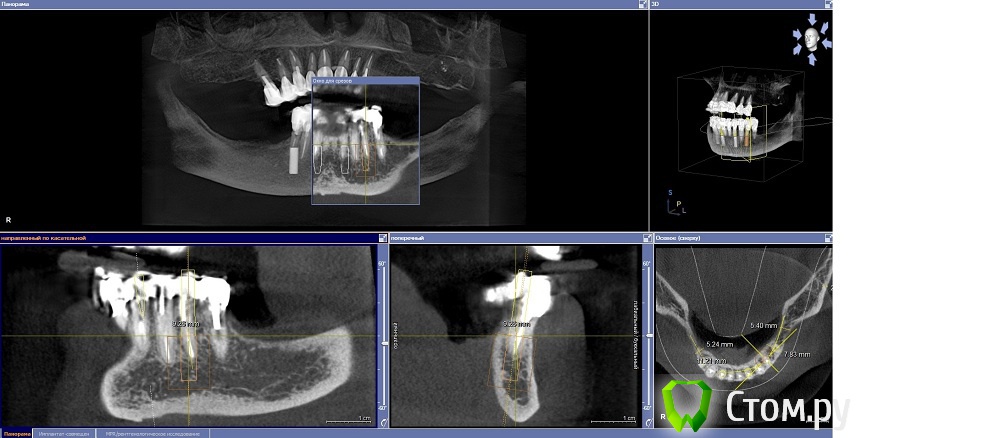

Dr.Sham Опубликовано 14 октября, 2014 Поделиться Опубликовано 14 октября, 2014 (изменено) Планируется удаление всех зубов на НЧ. Пациентка хочет несъемную конструкцию.Вот нарезка.Планируется имплантация Ankylos в позициях 46, 44, 42, 32, 34, 36.В боковых отделах дефицит всего.Думаю удалить зубы через один, чтобы на них временная конструкция держалась, а в промежутках имплантаты.В переднем отделе узко, либо узкие ФДМки, либо заглушка и в овоид край времянок или закрыть свободным трансплантатом.Что думаете?В боковых отделах вопрос...короткие имплантаты и НКР? От сложной костной пластики пациентка отказывается категирочески. Сверху пациентка так же хочет несъем. Поэтому все на 4-х, наверное, не самамя удачная конструкция здесь. Зубы сохранить никак, преп под десной местами по 3 мм. ну и дентин весь мягкий. Изменено 14 октября, 2014 пользователем Dr.Sham Ссылка на комментарий

Mane Опубликовано 15 октября, 2014 Поделиться Опубликовано 15 октября, 2014 Добрый вечер. Можно вариант Дмитрия. А можно и : Ваксап 12 зубов на н/чОртопедический шаблон на н/ч Операция: удаляете все сразу 4 имплантата 34-32-42-44 - по длиннее - чтоб торк точно был. В боковых отделах поставьте коротыши и НКР по толщине сделайте. перед установкой имплантатов, как сказал Дмитрий, выровняйте гребень во фронтальном отделе - чтоб с боковыми отделами не было большого перепада - коромысла. Срузу после операции нагружайте эти 4 имплантата несъемной конструкцией лабораторного изготовления. Если требуется, можно и по десне поработать в первую операцию. Удачи. На анкилозе есть же коротыши! 4 Ссылка на комментарий

Дмитрий Никитюк Опубликовано 15 октября, 2014 Поделиться Опубликовано 15 октября, 2014 Мысли в слух: планировать нужно, исходя из будущего протезирования обеих челюстей. Я посмотрел на верх и, учитывая возраст пациентки (69 лет), понимаю, что вряд ли там будет синус и 8 имплантатов. Там скорее всего будет или съёмный протез, или максимум 6 имплантатов (пусть топикстартер поправит, если не так). Поэтому на н.ч. вполне достаточно 4 импланта. Два из них под углом 30 °, с выходом платформ на область вторых премоляров, два других между ними (нет разницы в каких позициях). Почему не больше имплантатов? А зачем больше? Лучше эти деньги потратить на довольно дорогостоящую, но очень продуманную систему SmartFix. Каждый дополнительный имплантат будет лишь удорожать конструкцию и усложнять технологический этап. А 12 зубов на н/ч вполне достаточно. Ну и не будем забывать, что нижняя челюсть во время функции меняет геометрию, что вынуждает нас при дистально расположенных опорах делить конструкцию на части.Также от будущей судьбы верхнего зубного ряда зависит и материал постоянной конструкции на н/ч, но это будет потом. 1 Ссылка на комментарий

Dr.Sham Опубликовано 15 октября, 2014 Автор Поделиться Опубликовано 15 октября, 2014 Добрый вечер. Можно вариант Дмитрия. А можно и : Ваксап 12 зубов на н/чОртопедический шаблон на н/ч Операция: удаляете все сразу 4 имплантата 34-32-42-44 - по длиннее - чтоб торк точно был. В боковых отделах поставьте коротыши и НКР по толщине сделайте. перед установкой имплантатов, как сказал Дмитрий, выровняйте гребень во фронтальном отделе - чтоб с боковыми отделами не было большого перепада - коромысла. Срузу после операции нагружайте эти 4 имплантата несъемной конструкцией лабораторного изготовления. Если требуется, можно и по десне поработать в первую операцию. Удачи. На анкилозе есть же коротыши!Спасибо за отзыв. Теперь понял про коромысло ) 6,6 мм должны быть, но их нет в РФ. А 8 мм - уже не коротыши, при том, что коллеги рекомендуют на 2 мм заглублять. Ссылка на комментарий